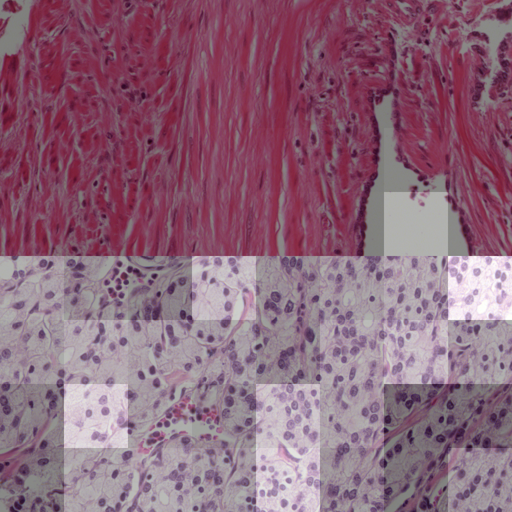

In a first analysis we use the Gleason dataset to create an artificial dataset for which the annotation per image patch is known. Each image in this dataset combines one image showing benign tissue and one image with malignant Gleason grade 5 tissue by stitching half of each together (see example in \figurereffig:fake_attention_example_img). For each image, the attention weights per patch are extracted from the MIL layer of eCaReNet. In the example it can be seen that the upper, malignant part, receives the highest attention weights, while in the benign tissue only relatively bright regions are highlighted. This may be because white regions correspond to glands, which are an important structure to distinguish benign from malignant tissue (see also \figurereffig:apd_att). A boxplot of the attention weights of all 12 example images is shown in \figurereffig:fake_attention_example_box. The attention weights for malignant patches are significantly higher than for benign patches. The original images that were stitched together are neither part of the training nor of the validation or test sets and give an unbiased estimate of importance.

As an additional example for the experiment described in \sectionrefsec:attention, \figurereffig:apd_att is provided. Also here it is shown that the malignant patches (in the lower part of the image) receive higher attention weights.

fig:apd_att